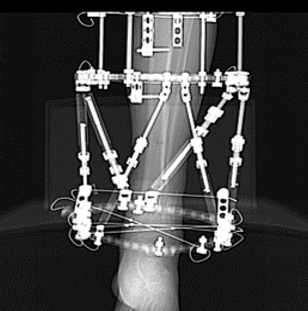

Fine wire circular fixator

Name the technique of fixation